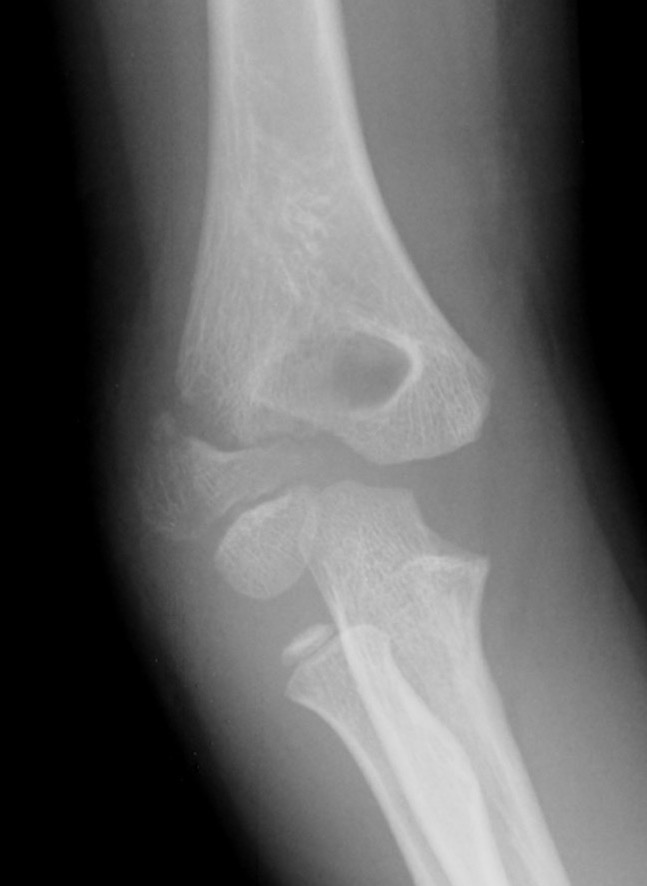

X-ray

Undisplaced

- typically metaphyseal flake

- looks minimally displaced on AP and lateral

- perform an internal oblique x-ray to exclude displacement

Injured left elbow v injury right elbow